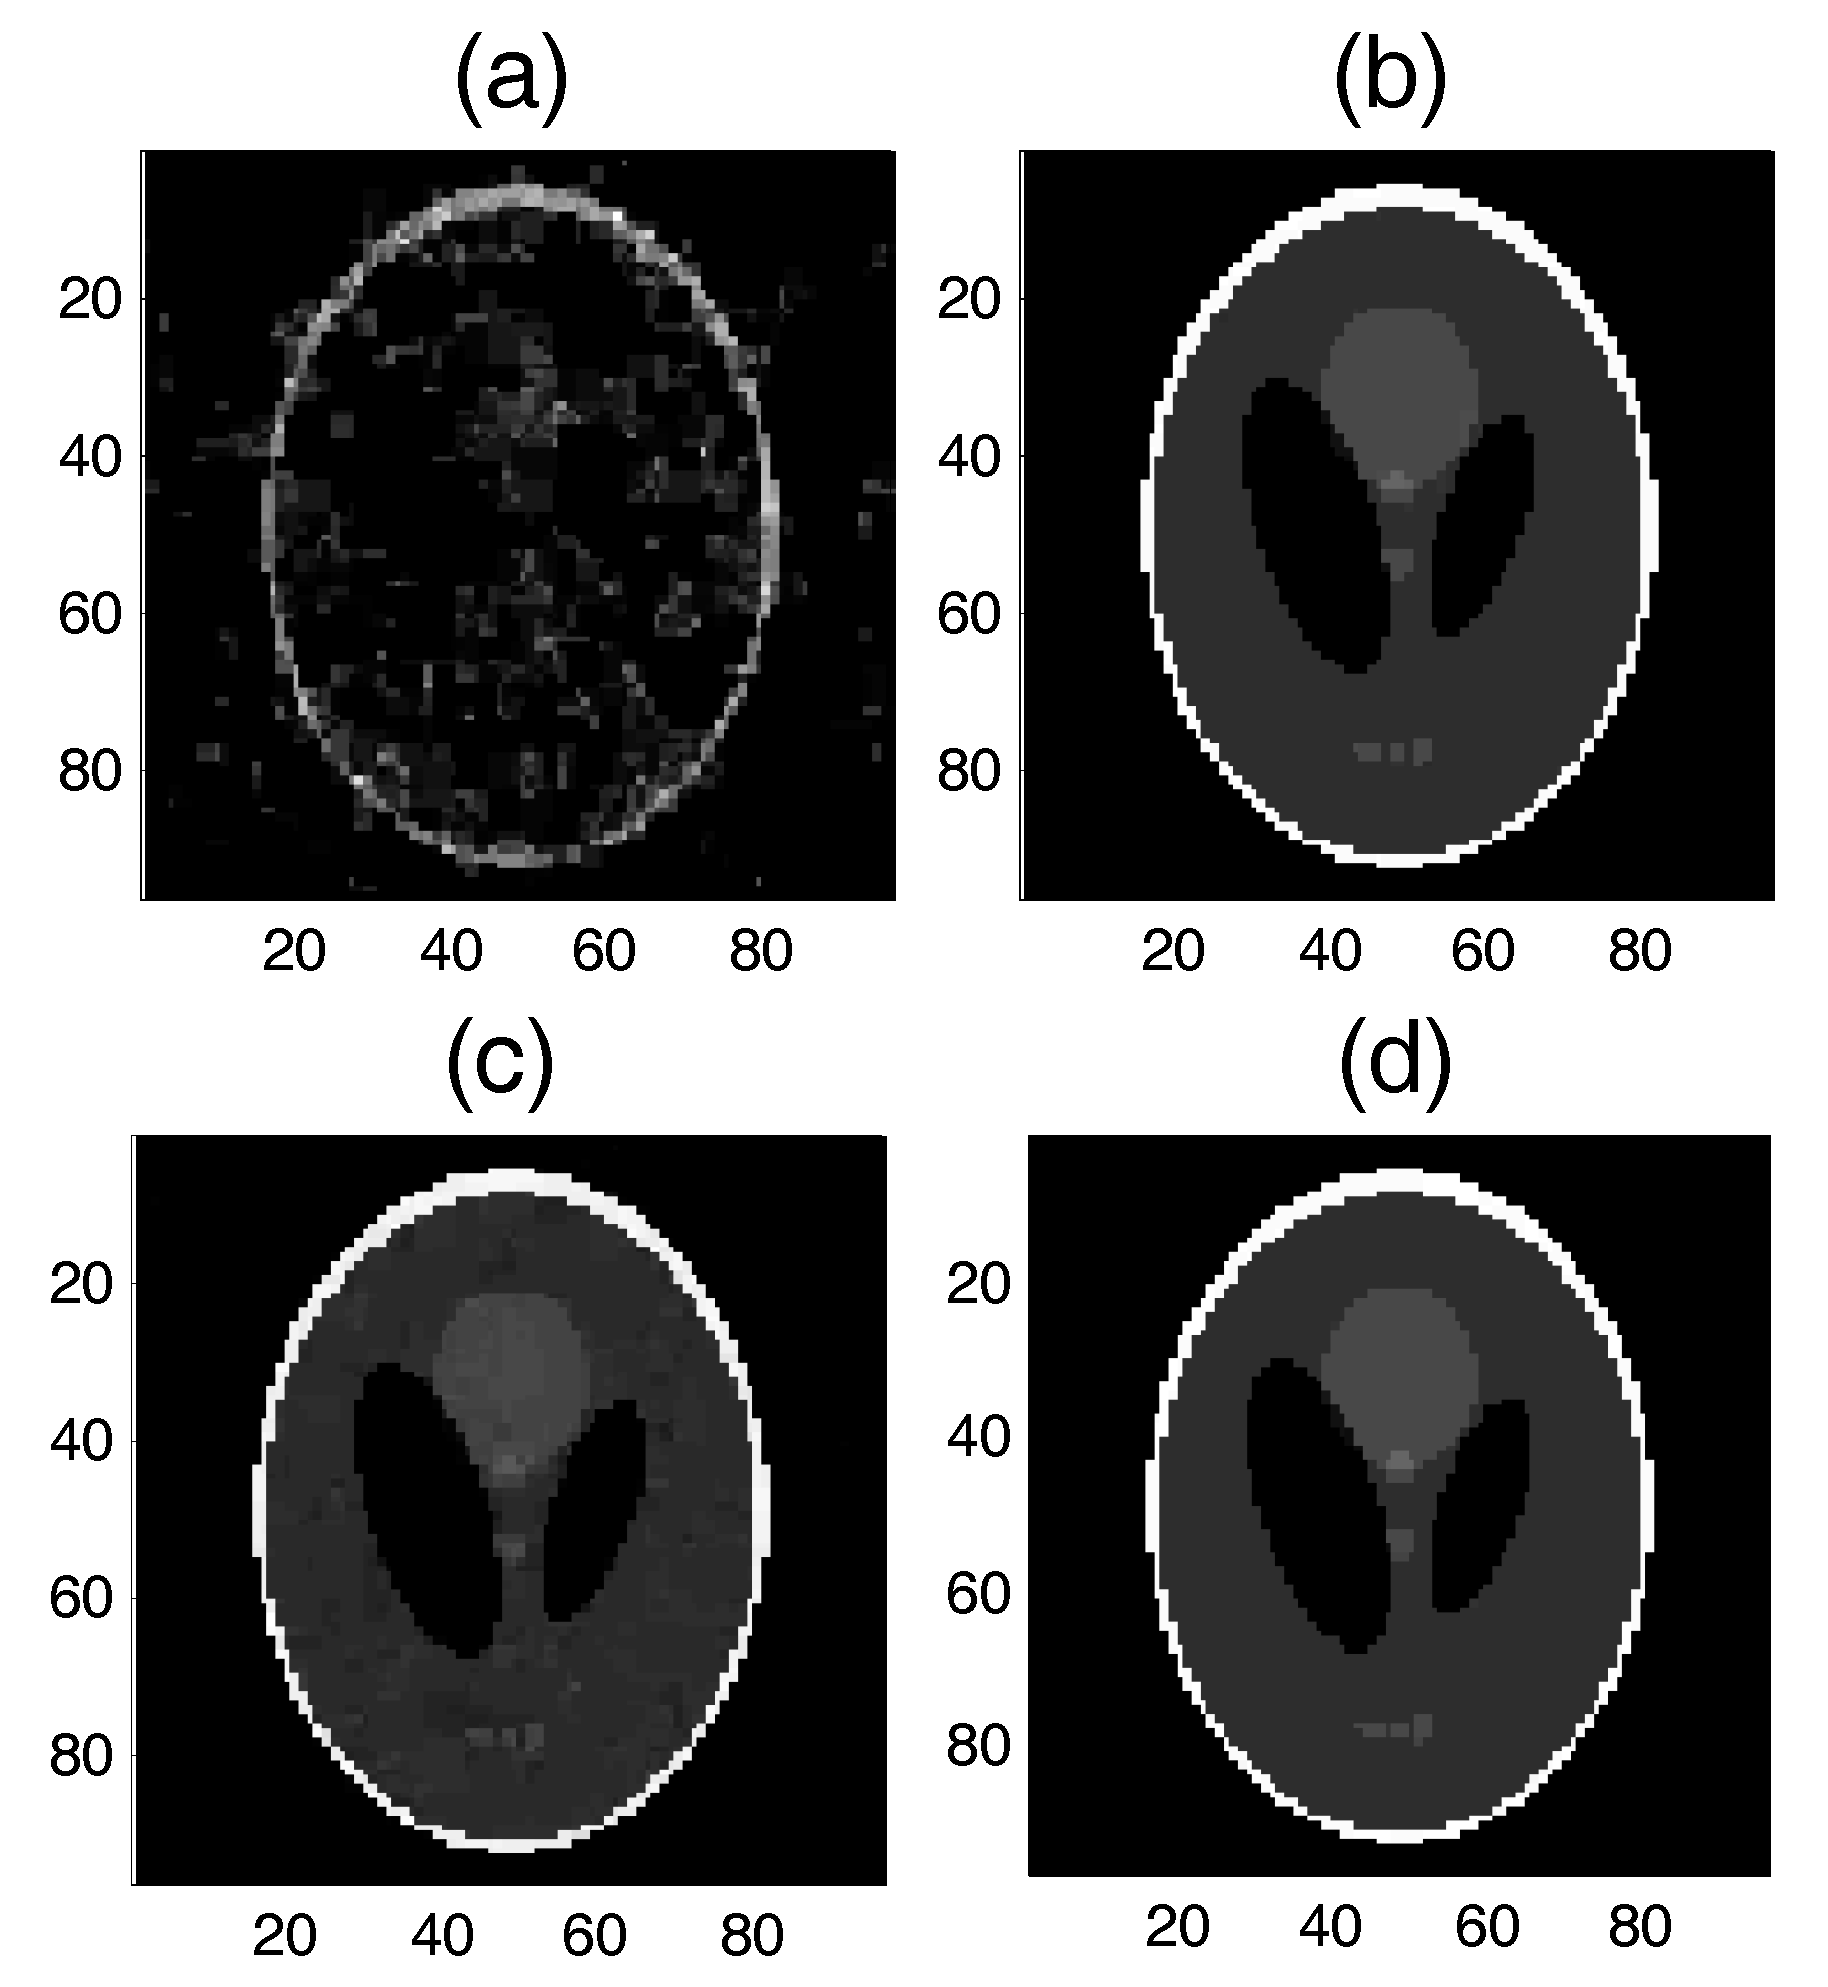

5.2.1. Test 1 for the Shepp-Logan Model